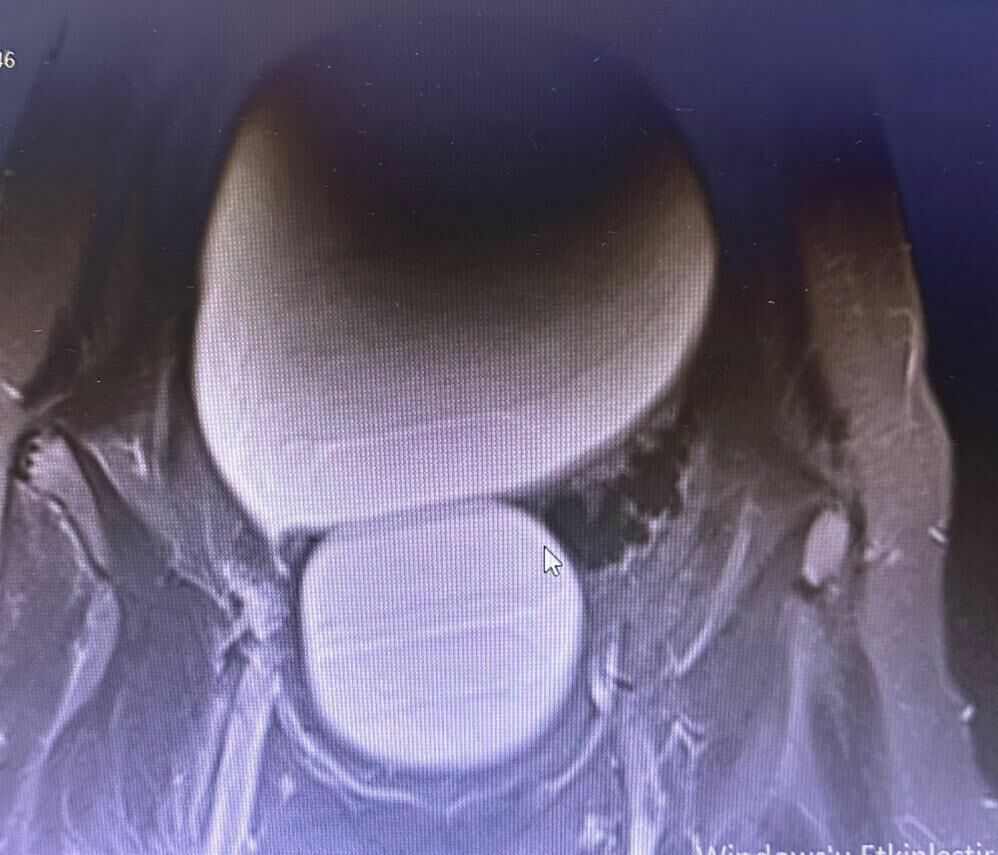

Sivas'ta yaşayan 12 yaşındaki N.B. isimli genç kız, şiddetli karın ağrıları ve düzensiz adet kanamaları şikayetiyle hastaneye başvurdu. Yapılan detaylı tetkikler sonucunda, genç kızın karın bölgesinde yaklaşık 25 santimetre çapında, kavun büyüklüğünde bir kist olduğu tespit edildi.

Medicana Sivas Hastanesi'nde Çocuk Cerrahisi Uzmanı Op. Dr. Mahmut Aluç tarafından gerçekleştirilen başarılı bir operasyonla, genç kızın sol yumurtalığında bulunan ve karaciğere kadar uzanan devasa kist içerisindeki 1.6 litre sıvı boşaltıldı ve kist başarıyla çıkarıldı. Sağlığına kavuşan genç kız, operasyonun ardından taburcu edildi.

Operasyonu gerçekleştiren Op. Dr. Mahmut Aluç, kistten yaklaşık 1.6 litre sıvı boşaltıldığını belirterek, 'Karın ağrısı ve düzensiz adet şikayetiyle başvuran hastamızın detaylı tetkikleri sonucunda, karın içerisinde yaklaşık yirmi beş santimetrelik bir kitle tespit ettik. Sol över kökenli bir kist olduğunu fark ettik. Gerekli incelemeler yapıldıktan ve ailenin onayı alındıktan sonra hastayı operasyona aldık. Karaciğere kadar uzanan bir kisttik yapı vardı. Yaklaşık 1.6 litre sıvıyı boşaltarak kisti tamamen eksize ettik. Hastamız şifa ile taburcu edildi. Patoloji sonucumuz da iyi huylu olarak geldi' dedi.